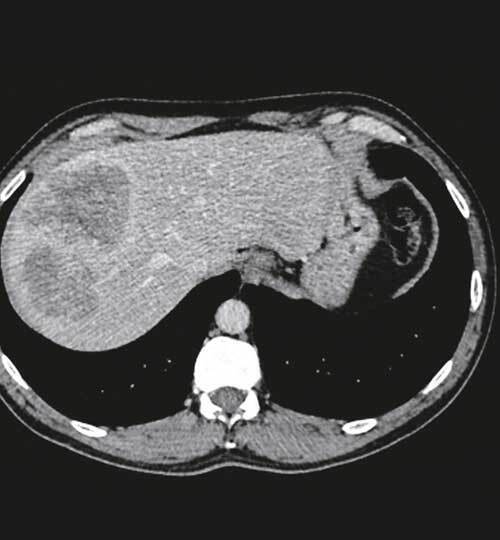

Faouzi I, Lucidarme O. Bilan initial et stadification du cancer du rectum.Rev Prat 2022;72(1);38-42.